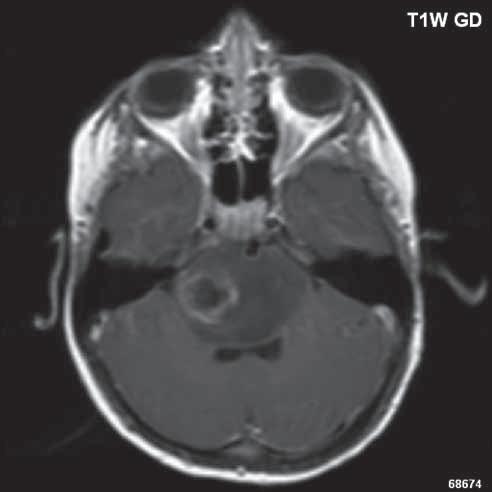

Zobrazení

D-W malformace je charakterizována hypoplazií vermis mozečku, rozšířením IV. mozkové komory, která se často cysticky vyklenuje dorzálně a může imitovat arachnoidální cystu, rozšířením zadní jámy lební a vysokým úponem tentoria s confluens sinum nad lambdovým švem. Okcipitální kost může být vlivem tlakových změn remodelována, existují i případy s porušením její kontinuity a encefalokélou. Hydrocefalus pozorujeme v 80 %, častá je přítomnost dysgeneze corpus callosum, schizencefalie.

Obr. I.1.8a Dandy-Walkerova malformace, rozšířená IV komora (tvar klíčové dírky)

Obr. I.1.8b Dandy-Walkerova malformace, rozšířená IV komora široce komunikující s cisterna magna, hypotrofie mozečku (snímky zapůjčeny z archivu prim doc MUDr M Mechla, Ph D, MBA)

Obr. I.1.8c Dandy-Walkerova malformace, rozšířená IV komora široce komunikující s cisterna magna, hypotrofie mozečku (snímky zapůjčeny z archivu prim doc MUDr M Mechla, Ph D, MBA); stejný pacient jako na obr I 1 8b

Obr. I.1.8d Dandy-Walkerova malformace, rozšířená IV komora široce komunikující s cisterna magna, hypotrofie mozečku, vysoký úpon tentoria (šipka) (snímky zapůjčeny z archivu prim doc MUDr M Mechla, Ph D, MBA); stejný pacient jako na obr I 1 8b, c